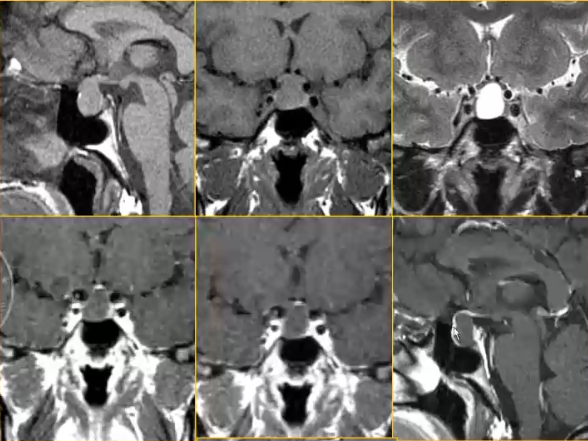

Rathke裂囊肿

Rathke囊肿是胚胎Rathke囊的上皮残余,壁薄,仅1-2层细胞;囊壁有分泌功能,液体增多形成囊肿。囊液可为浆液性或粘液性。可发生于任何年龄。部位:鞍上鞍内均存在(75%),鞍内(20-25%),仅在鞍上(<5%),典型部位在垂体前后叶间。

CT、MRI表现:

1. 垂体前后叶间的囊性病变

2. 囊肿信号与囊液的性质有关

3. 增强后无强化

Rathke裂囊肿位于垂体前后叶间,信号与囊液的性质有关,对前后叶及邻近结构产生压迫(如下图)